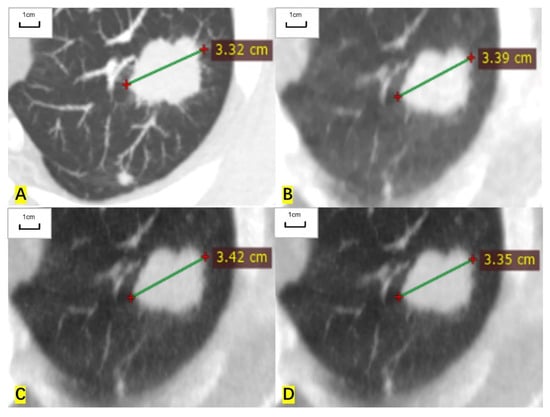

Figure 4.

A 64-year-old man had a solid nodule in the middle lobe of the right lung and the histological result was lung adenocarcinoma. (A) The long diameter measured on the contrast-enhanced CT is 6.94 mm. (B) The long diameter measured on the ASIR-V-80% image is 8.02 mm, overestimated by 15.6% compared with that of contrast-enhanced CT. (C) The long diameter measured on the DLIR-M image is 8.21mm, overestimated by 18.3%. (D) The long diameter measured on the DLIR-H images is 7.62 mm, overestimated by 9.8%.

For RECIST-defined nonmeasurable pulmonary target lesions, the correlation coefficient of measured diameter between ULDCT and contrast-enhanced CT was 0.977 (0.970 to 0.982), 0.987 (0.983 to 0.990), and 0.995 (0.994 to 0.996) for ASIR-V-80%, DLIR-M, and DLIR-H images, respectively. For mediastinal lymph nodes, the correlation coefficient was 0.937 (0.898 to 0.962), 0.939 (0.901 to 0.963), and 0.970 (0.951 to 0.982), respectively. For nonmeasurable hilar lymph nodes, the correlation coefficient was 0.994 (0.966 to 0.999), 0.969 (0.835 to 0.995), and 0.997 (0.982 to 0.999), respectively. The measured diameters of nonmeasurable target lesions in ULDCT were also highly correlated with those in contrast-enhanced CT (Table 4, Figure 4 and Figure 5).